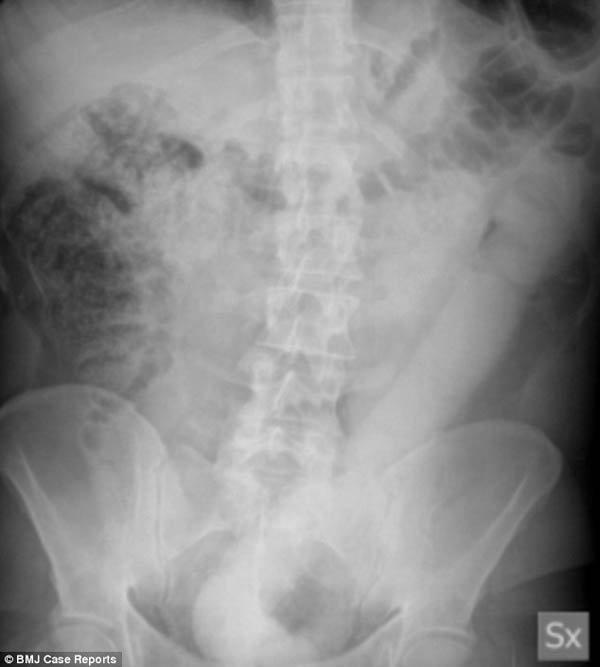

Chiếc dương vật giả dài 60cm nằm gọn trong đại tràng

Sau khi tiến hành xác định vị trí của dị vật, dù thử nhiều biện pháp khác nhau, các bác sĩ cũng gặp khó khăn khi rút nó ra vì kích cỡ quá lớn và bề mặt trơn tuột. Trong tình huống xấu nhất, có thể bệnh nhân sẽ phải tiến hành phẫu thuật để loại bỏ dị vật mắc kẹt. Tuy nhiên, sau một hồi thảo luận, nhóm bác sĩ đã bàn bạc và chế tạo một công cụ mới hoạt động như chiếc dây thòng lọng để kéo dị vật ra và đã thành công.

Tiến sĩ Dioscoridi người trực tiếp điều trị cho bệnh nhân cho biết: “Cuối cùng chúng tôi đã thành công trong việc cải tiến máy nội soi để có thể cài được chiếc dây chắc chắn vào mép của dương vật giả và kéo nó ra. Chiếc dây làm cho vật thể có thể tách khỏi đại tràng và được lôi ra một cách dễ dàng".